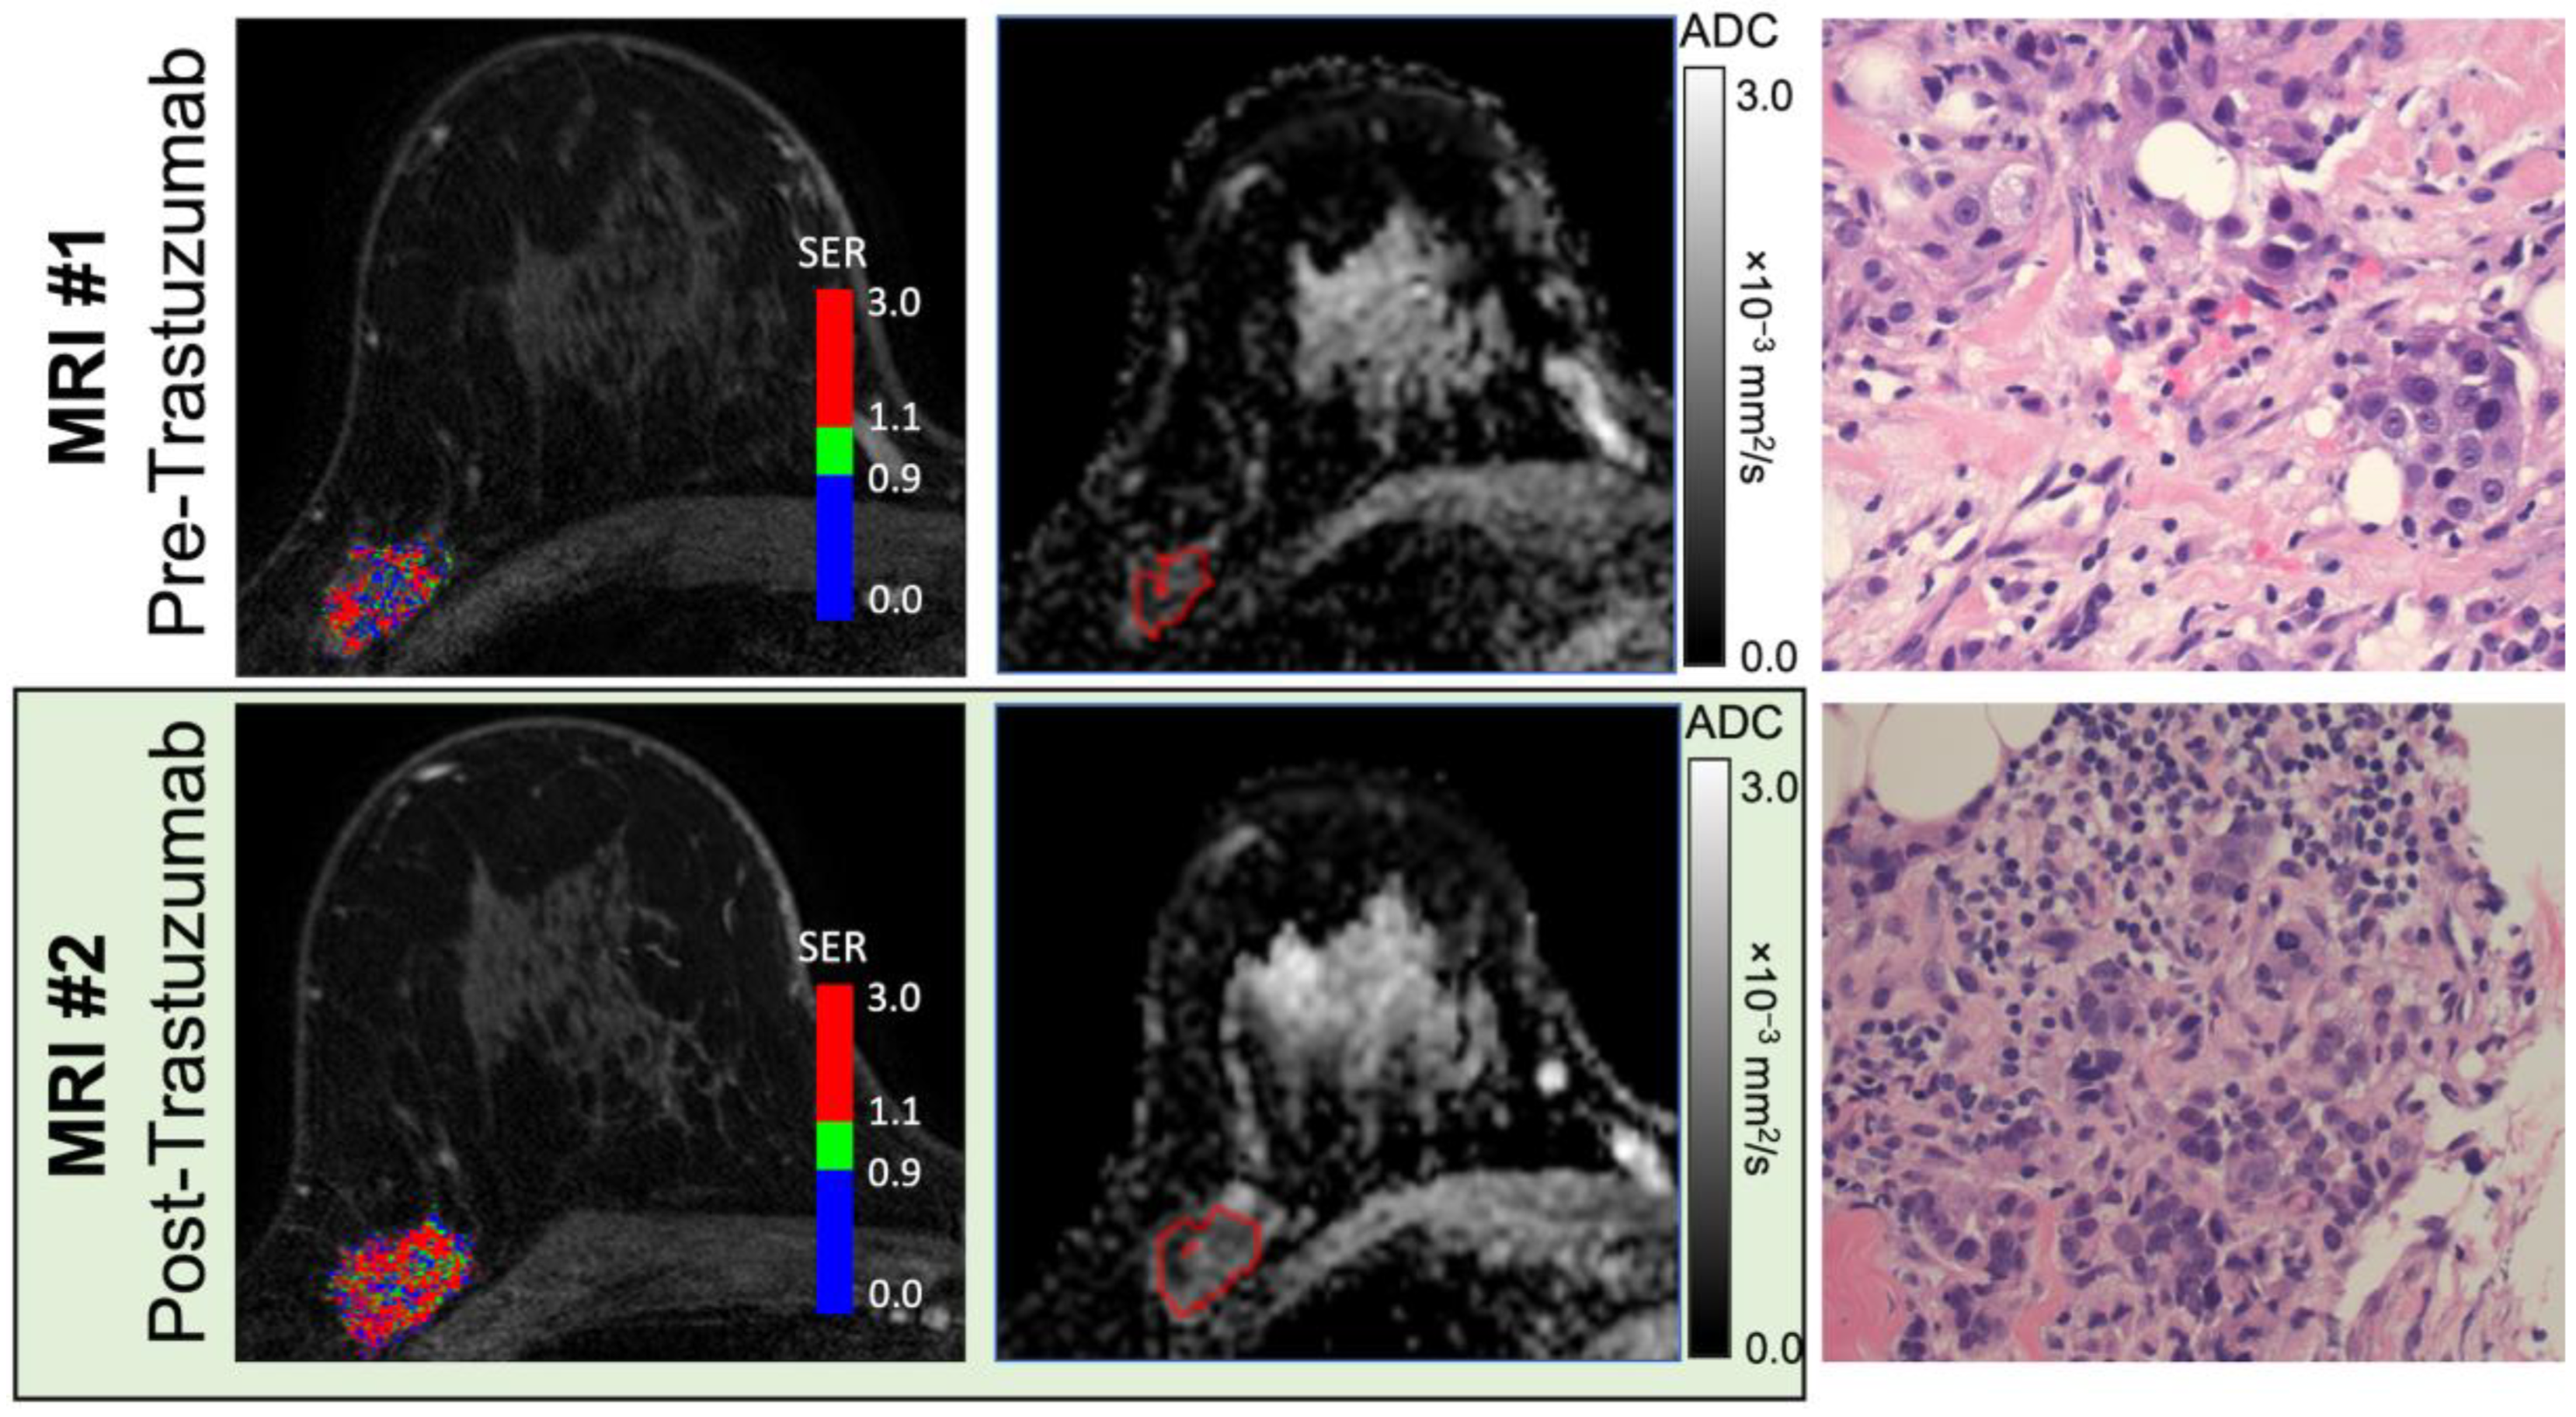

3.2. Peak PE and WF Correlate with an Immune Response Post-Trastuzumab Administration

To investigate whether imaging features were associated with treatment-induced immune response, pre- and post-trastuzumab MRIs were collected and analyzed. For this study, immune response was defined by TILs. A representative set of MRI data and histology are shown in Figure 2; individual patient data are available in Table S1. The percentage of stromal TILs increased (defined as an increase greater than 1 decile) after treatment with trastuzumab in 6 out of 13 patients, with the median TILs going from 6% to 20% in the cohort (p < 0.01, Figure 3A). When stratified by hormone-receptor status, four out of seven estrogen receptor (ER)-negative patients had an increase in TILs with trastuzumab treatment and two out of the five evaluable ER-positive patients had an increase in TILs (Figure 3B and Figure S1). Two ER-negative and one ER-positive patient had TIL-enriched (TILs ≥ 30%) tumors at baseline.

Figure 2. Paired pre- and post-treatment MRI and histology assessments in a 51-year-old woman with Grade 3 ER+/HER2+ invasive ductal carcinoma (Patient ID #13). Shown are representative signal enhancement ratio maps generated from dynamic contrast-enhanced MRI (left), apparent diffusion coefficient maps from diffusion-weighted MRI (middle; tumor region-of-interest is shown), and hematoxylin and eosin (H&E)-stained tissue specimens at ×400 magnification (right) obtained before and after a run-in treatment of trastuzumab (top and bottom row, respectively). Prior to treatment, quantitative MRI analysis measured functional tumor volume (fTV) of 2.1 cc, washout fraction 35%, initial peak percent enhancement (PE) 207%, peak signal enhancement ratio (SER) 1.87, and apparent diffusion coefficient (ADC) 0.61 × 10−3 mm2/s. MRI obtained 14 days after treatment demonstrated increases in both vascularity- and cellularity-related metrics (fTV 5.0 cc, washout fraction 47%, PE 231%, SER 2.17, and ADC 0.66 × 10−3 mm2/s). Pathologist assessment of stromal tumor-infiltrating lymphocyte (TIL) level identified an increase from pre- (≤9%) to post-treatment (10–19%), reflecting a treatment-induced immune response.